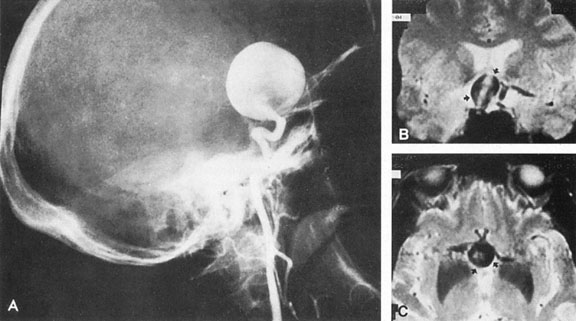

Most such aneurysms expand upward and forward, becoming located primarily anteriorly (Fig. 4). The optic nerves rise upward form the optic canal and may be inclined at a 45-degree angle such that the chiasm is more superiorly, as well as posteriorly, placed. It may be expected that uniocular ipsilateral visual loss would occur and progress before the contralateral field is involved because of chiasmal compression and before opposite nerve damage ensues. Although rapid visual loss has been reported, a longer duration (even years) is the rule. Rarely, the aneurysm may be more posteriorly placed or the chiasm more anteriorly fixed, resulting in initial involvement of the optic tract.20

Fig. 4. Giant suprasellar (supraclinoidal) aneurysms. A: Carotid arteriogram (lateral view) shows a huge aneurysm of the internal carotid artery in a 59-year-old woman with progressing visual loss. Coronal (B) and axial (C) magnetic resonance imaging sections of a similar case. Note partial thrombus formation (TR, 2100 ms; TE, 80 ms).